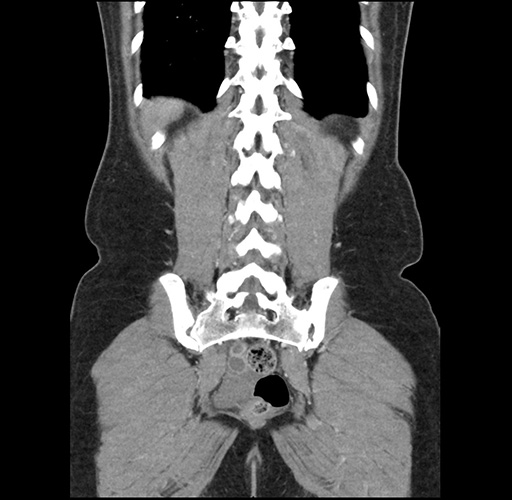

Imaging Analysis

Look through the patient's CT scan to identify any areas of concern for the necessary procedure.

Based on your CT findings, which issue(s) would give reason for "planned slowing down moment(s)" in this case?